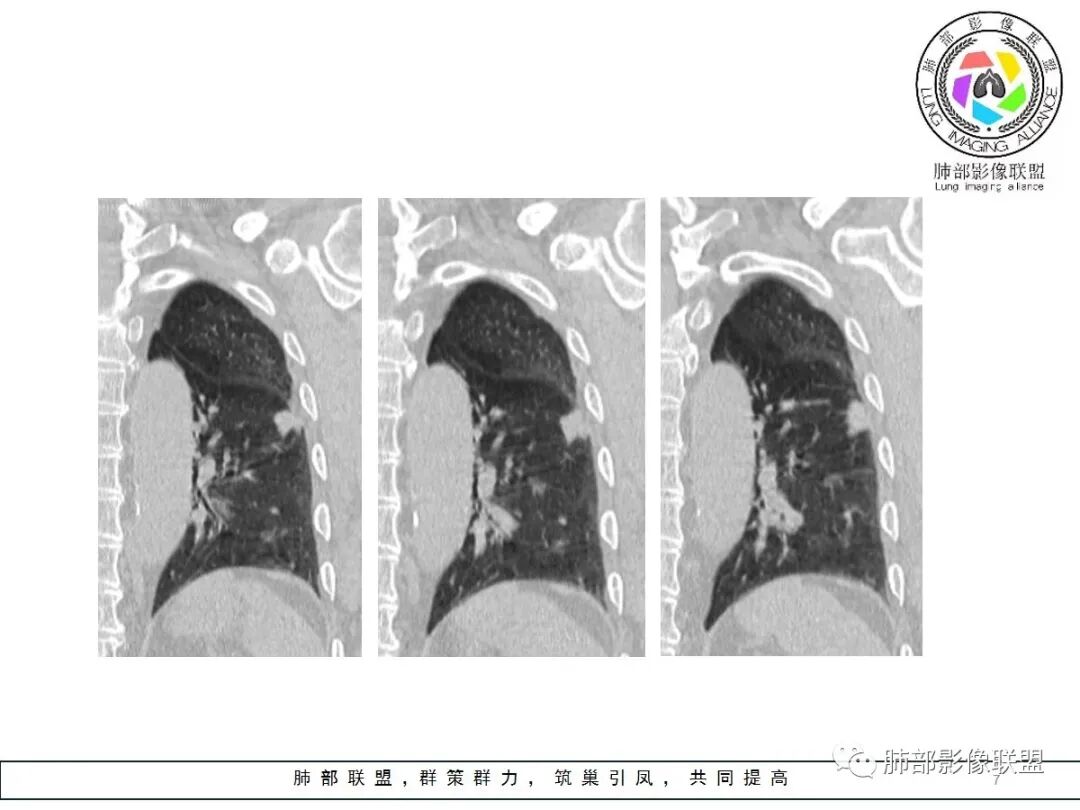

边缘平直

宽基底与胸膜相连

这条血管让我不踏实,像脐凹征吗?

其他的都是炎性特点,恶性待排吧

日常工作中抗炎后复查,看病灶的变化

就是这个脐凹征有恶性的特点,所以恶性肯定不能排除